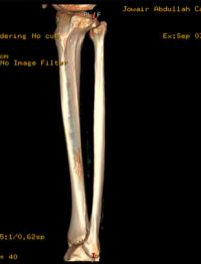

Radiographs taken in the ED demonstrated a lesion with subtle sclerosis in the anterolateral midshaft of the left tibia (Figure 1). A CT scan of the left leg revealed a focal cortical lesion with central calcification suggestive of an osteoid osteoma in the anterior aspect of the left mid-tibial shaft. Proximal to this lesion, another similar lesion with a periosteal reaction was noted just distal to the tibial tuberosity (Figures 2-4).

Figure 4: Preoperative 3D Reconstruction CT Scan of the Left Tibia. A 3D reconstruction CT scan providing a comprehensive view of the left tibia. The cortical lesion indicative of osteoid osteoma is visible, along with the surrounding bone reaction. This view aids in surgical planning and understanding the spatial relationship of the lesion within the bone structure